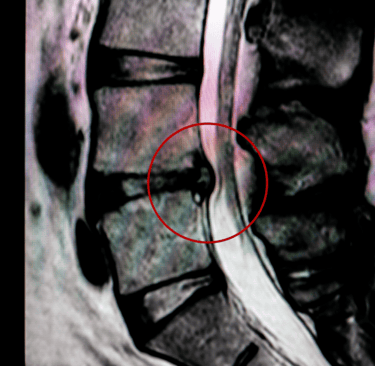

قد تؤدي بروزات الأقراص القطنية، أو الانزلاقات الغضروفية، أو التغيرات التنكسية في الأقراص الفقرية إلى الضغط على جذور الأعصاب التي تُشكّل العصب الوركي، مما يسبب ألمًا منتشرًا يمتد إلى الساق.